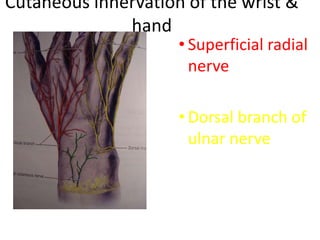

- Naming the bones, joints, tendons, nerves and skin landmarks of the hand and wrist.